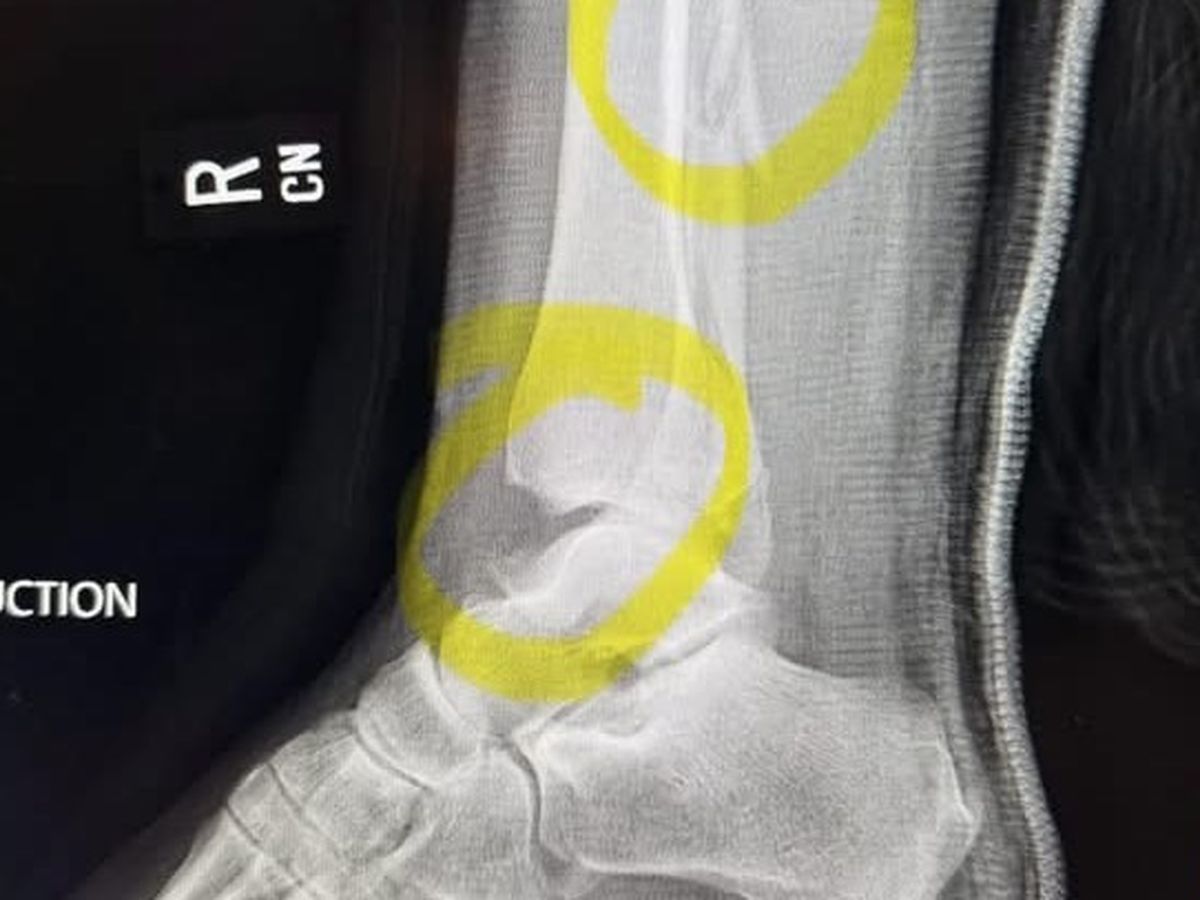

She was up early on Tuesday, 1/14, to feed everyone and tripped over her blind kitty’s favorite box. The photo above shows the 2 breaks - tibia and ankle. She had surgery a few hours later and may get out of the hospital tonight or tomorrow but is unable to work. Please donate whatever you can to help Sarah get back on her feet (not literally yet).